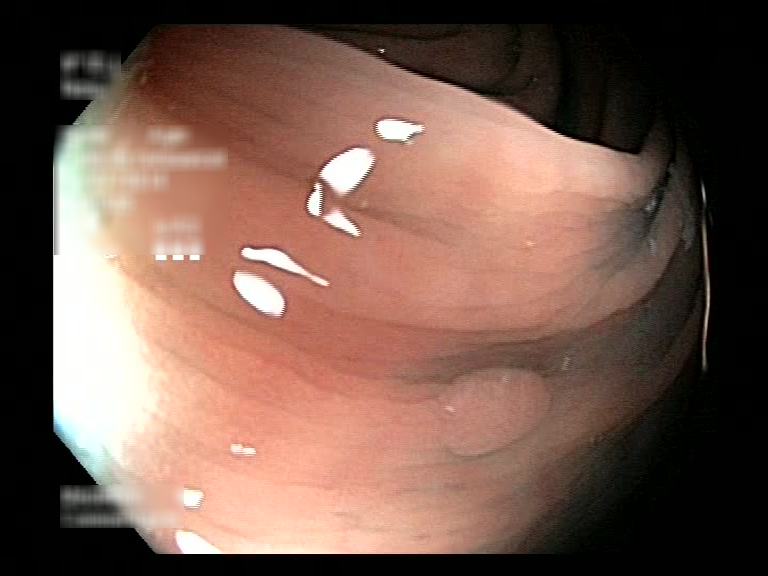

| Lesion | White Light Frame | NBI Frame | White Light Video | NBI Video | Camera Calibration |

| hyperplasic_01 |  |

|

WL.mp4 | NBI.mp4 | cam.xml |